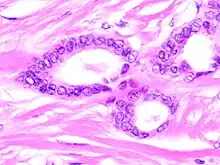

Histopathology of tubular carcinoma, high magnification, H&E stain. It shows the typical features of tubules lined by a single layer of cuboidal to columnar epithelial cells with small to intermediate sized nuclei low grade nuclei and sparse mitoses (grade 1).[1]

Tubular carcinomas are generally around 1 cm. or smaller, and are made up of tubules. They are usually low-grade.[2] Elastosis has been noted as common but is not present in all cases.[11]